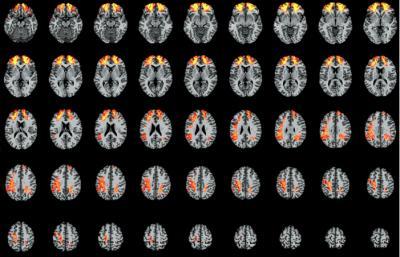

The researchers identified a network of brain areas in the frontal and parietal cortex that are essential to discourse comprehension.

Researchers compared the discourse comprehension abilities of patients with damage to specific brain regions relative to patients without damage to those regions. Each image here represents one slice of the brain and the highlighted areas are those that are important for discourse comprehension.